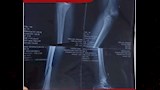

وكان مستشفى العامرية العام بالإسكندرية استقبل في قسم الطوارئ مصابًا بكسر في اليد اليسرى، وكسر في الساق اليمنى، إلى جانب كسور متعددة بعظام الوجه، ما استدعى تدخلاً جراحيًا فوريًا لإنقاذ حالته ومنع تفاقم المضاعفات.

وتمكن الفريق الطبي من تثبيت كسر اليد اليسرى باستخدام شريحتين ومسامير، بينما جرى تثبيت كسر الساق اليمنى بواسطة مسمار نخاعي، بالإضافة إلى تثبيت كسور الوجه باستخدام شريحة ومسامير، في عملية دقيقة تكللت بالنجاح.